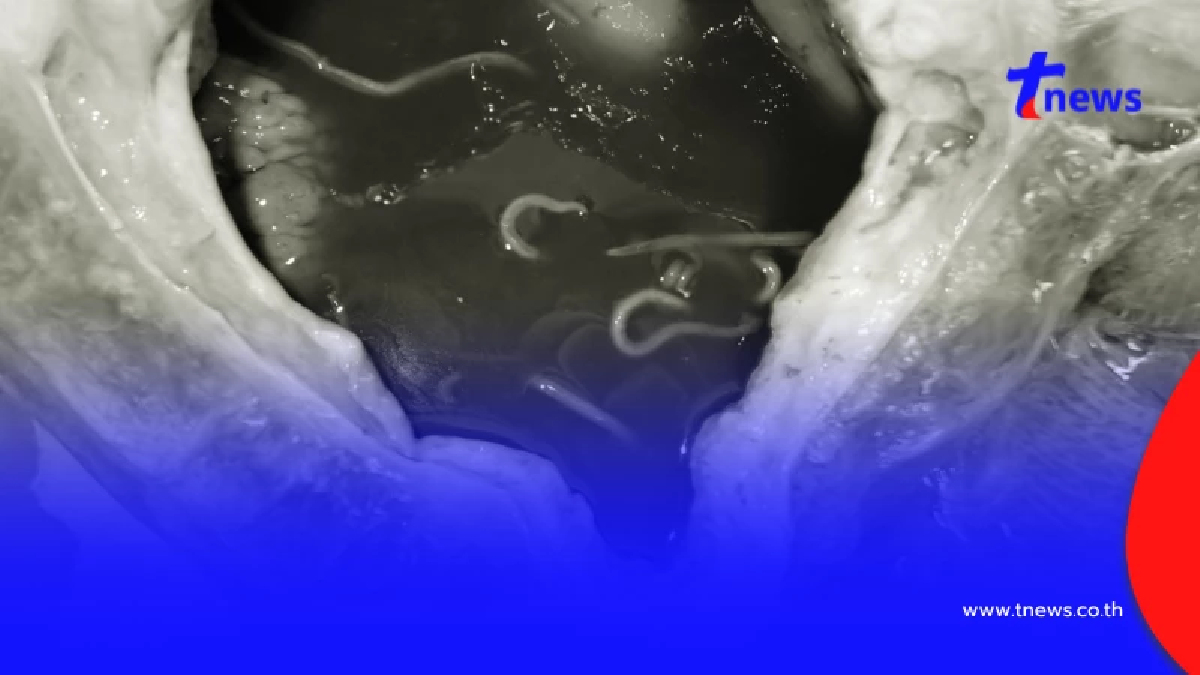

ผลการชันสูตรเบื้องต้นพบชั้นไขมันบาง (1.2–1.8 ซม.) และกล้ามเนื้อฝ่อเล็กน้อย บ่งชี้ถึงภาวะพร่องโภชนาการระบบทางเดินหายใจพบพยาธิใบไม้ในรูจมูกเล็กน้อย และเศษกรวดในหลอดลมกระเพาะอาหารว่างเปล่า มีเพียงของเหลวปนเศษหญ้าเล็กน้อย และพบพยาธิตัวกลมในกระเพาะและลำไส้เล็กจำนวนมาก (98 ตัว) ลำไส้ใหญ่มีอุจจาระอัดแน่นและค่อนข้างแห้ง